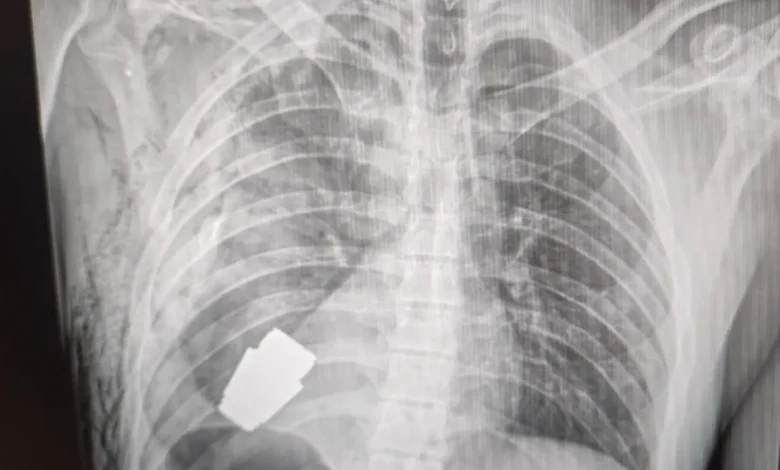

حالف الحظ والجهود الطبية أحد الجنود الأوكرانيين وبقي على قيد الحياة بعد أن استقرت قنبلة حية في جذعه خلال معركة في باخموت بأوكرانيا، وكان لا بد من التدخل لإزالتها جراحيا.

واضطر الجراح الأوكراني اللواء أندري فيربا إلى إجراء الجراحة علما أن القنبلة اليدوية يمكن أن تنفجر في أي لحظة.

وأكد حاكم المنطقة، سيرهي بورزوف، في منشور على “فيسبوك” ليلة الاثنين أن “أطبائنا العسكريين أجروا عملية لإزالة قنبلة غير منفجرة من جسد جندي”.

ومع ذلك، قال بورزوف إن الدكتور فيربا كان قادرا على إجراء الجراحة بنجاح وإزالة القنبلة اليدوية.

وأضاف بورزوف أن “التدخل العملياتي كان ناجحا وتم إرسال الجندي المصاب لإعادة التأهيل والتعافي”.